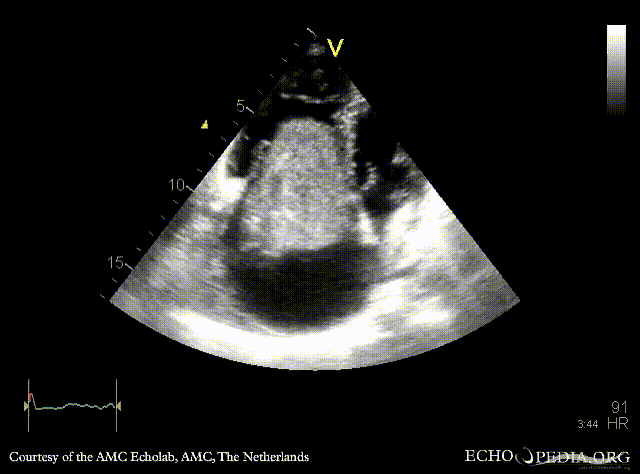

Case 152